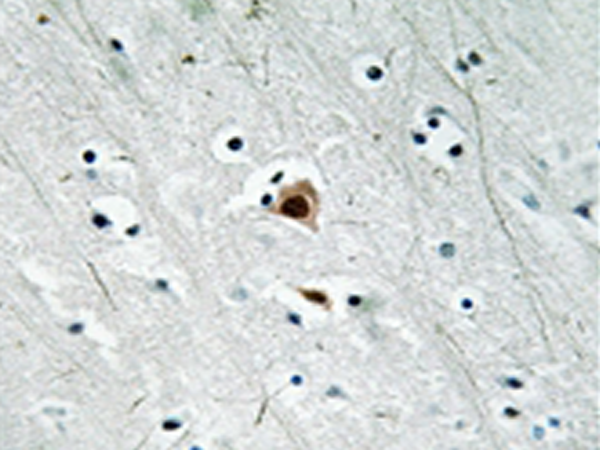

IHC positive control: |

Human brain tissue |

IHC Recommend dilution: |

50-100 |